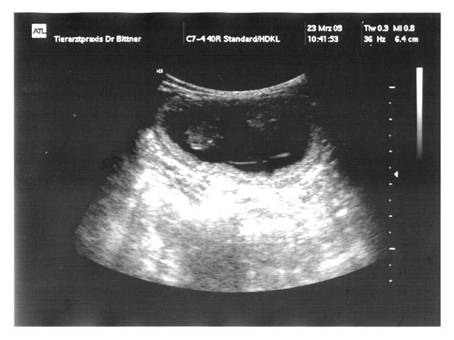

23.03.2009  Tag 36  |

:  |

MiniFee  |

hatte heute endlich ihren Ultraschall-Termin …

… und 2 Babys waren ganz klar

zu erkennen. Ich bin so

happy, dass MiniFee jetzt tragend ist !!!  |